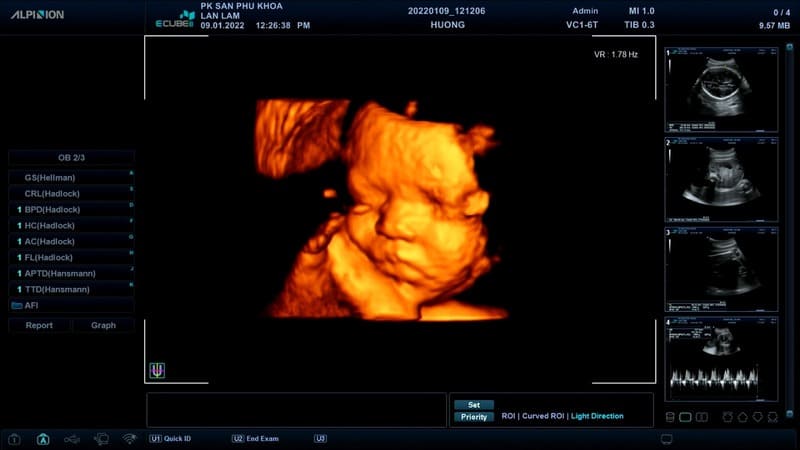

Phòng Khám Sản – Phụ Khoa Bamboo Care là địa chỉ uy tín được nhiều chị em tin tưởng trong chăm sóc sức khỏe sinh sản tại Vinh . Đơn vị chuyên khám và điều trị toàn diện các bệnh lý sản – phụ khoa, mang đến giải pháp an toàn và hiệu quả. Bamboo Care nổi bật với dịch vụ siêu âm thai 5D HD Live hiện đại, giúp mẹ bầu quan sát rõ nét hình ảnh thai nhi. Ngoài ra, phòng khám còn cung cấp dịch vụ tư vấn và điều trị vô sinh, hiếm muộn bằng các phương pháp tiên tiến. Bên cạnh đó, Bamboo Care còn triển khai các biện pháp tránh thai công nghệ cao, hỗ trợ chị em chủ động bảo vệ sức khỏe và hạnh phúc gia đình.

Phòng khám được đầu tư hệ thống máy móc tiên tiến, đáp ứng tiêu chuẩn an toàn và chất lượng. Đặc biệt, dịch vụ siêu âm thai 5D HD Live mang lại hình ảnh rõ nét, giúp theo dõi sự phát triển của thai nhi chính xác hơn. Máy xét nghiệm và các thiết bị hỗ trợ cũng đảm bảo độ chính xác cao trong chẩn đoán bệnh lý. Việc ứng dụng công nghệ hiện đại giúp bác sĩ đưa ra kết quả nhanh chóng, giảm thiểu sai sót. Đây là yếu tố quan trọng tạo nên uy tín của Bamboo Care.